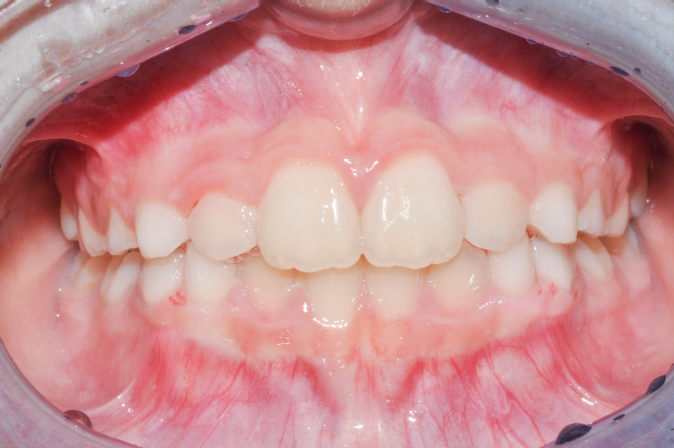

The patient presented with a skeletal Class I relationship and a mesofacial growth pattern, indicating balanced sagittal and vertical skeletal proportions. Dental examination revealed a Class I molar and canine relationship bilaterally. The patient was in the mixed dentition phase. Significant dental crowding was observed in both arches, consistent with a dentoalveolar discrepancy. Midline deviations were present, affecting dental symmetry and occlusal harmony. The maxillary lateral incisors were in crossbite, contributing to anterior transverse discrepancy and functional imbalance.

Periodontal evaluation revealed early signs of periodontal disease, primarily affecting tooth 41. Radiographic assessment demonstrated root convergence of teeth 11 and 21, indicating compromised root parallelism. Overall, the initial presentation was characterized by dentoalveolar crowding, transverse discrepancies, occlusal asymmetries, and early periodontal involvement within an otherwise favorable skeletal framework, requiring a carefully planned orthodontic approach to ensure functional stability and periodontal preservation.